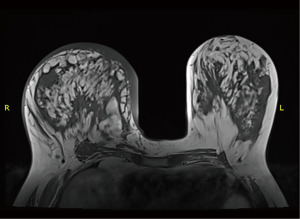

Retrospectively, we reviewed the patient’s mammogram, MRI and CT scan. All the images were consistent with a bilateral RS which is more obvious on the right side as the muscle fibers were longer and wider (Figures 2-4).